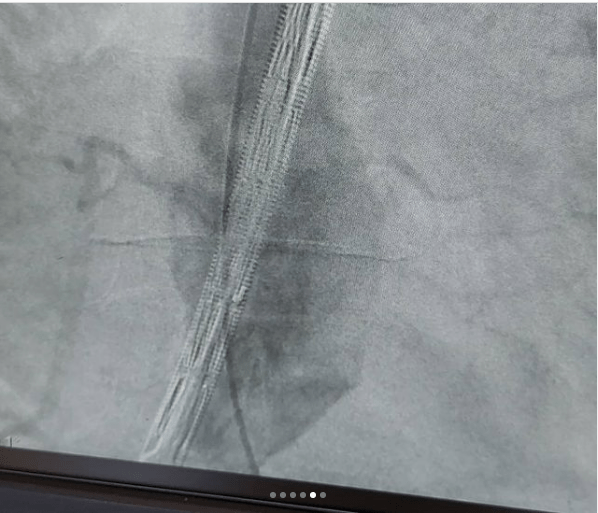

این بیماران با احساس ضربانات مداوم در شکم و درد و گاهاً بدون علامت در معرض خطر پارگی رگ اصلی بدن به نام آئورت ومرگ ناگهانی هستند .دیروز در کمتر از یکساعت بدون جراحی ، استنت هایی که پوشش دیواره ای دارند را مثل لوله داخل ناحیه آنوریسم/یا گشاد شده، تعبیه کردیم و آئورت به سایز نرمال برگشت.